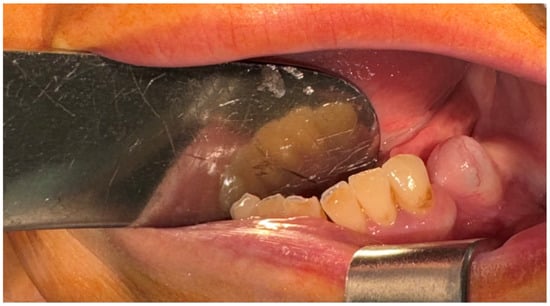

2.4. Second Surgical Intervention

2.5. Third Surgical Intervention